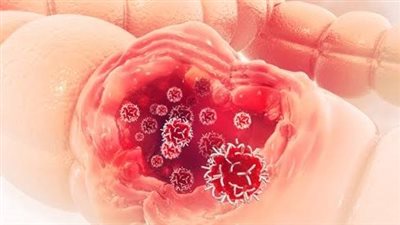

هل سرطان القولون مميت؟، سؤال تعتمد الإجابة فيه على الحجم الفعلي للورم، فمن المهم جدا الخضوع للفحص في الوقت المناسب في حالة ظهور أعراض سريرية على وجود سرطان القولون مثل وجود ألم مستمر في البطن، ومشاكل في التبرز، ووجود دم أو قيح في البراز.

وحول هل سرطان القولون مميت؟، عندما يتم اكتشاف المرض في مرحلة مبكرة، فإن متوسط البقاء على قيد الحياة لمدة خمس سنوات هو 92٪، بحسب العلماء، وهذا يعني أنه عند تنفيذ خطة العلاج المناسبة، فإن أكثر من 92٪ من المرضى سيعيشون بنجاح بعد ذلك لأكثر من خمس سنوات، حسبما كشف تقرير صادر عن المعهد الوطني للسرطان يتبع معاهد الصحة الوطنية الأمريكية.

تعتمد توقعات الحياة على مدى تغلغل الورم الخبيث في جدار الأمعاء، وفي المرحلة 2a يؤثر المرض على جدار الأمعاء كله، لكنه لا يتجاوزه، ويمكن فصل موطن الورم بوضوح عن الأنسجة المحيطة، ما يزيد من فعالية العلاج الجراحي.

في المرحلة b2، من الممكن ينتقل الورم إلى الأعضاء المجاورة - الكبد، والمثانة، والرحم لدى النساء.

ووفقًا للمعهد الوطني للسرطان، فإن متوسط البقاء على قيد الحياة لمدة خمس سنوات في هذه المرحلة من سرطان القولون والمستقيم يصل إلى 87٪ في المرحلة 2a و63٪ في المرحلة 2b.